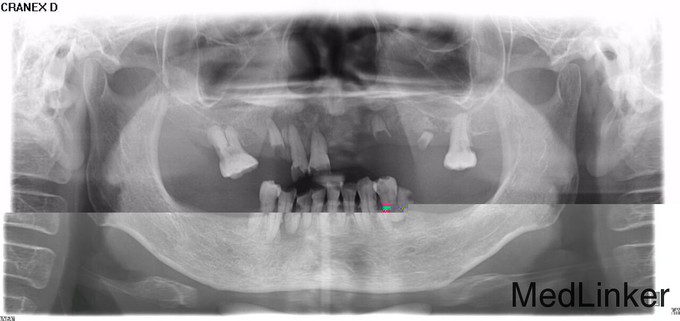

1110全口多颗牙缺失的治疗与修复光12

口内多颗牙剩余牙根,要求镶牙

左上后牙多颗牙缺失